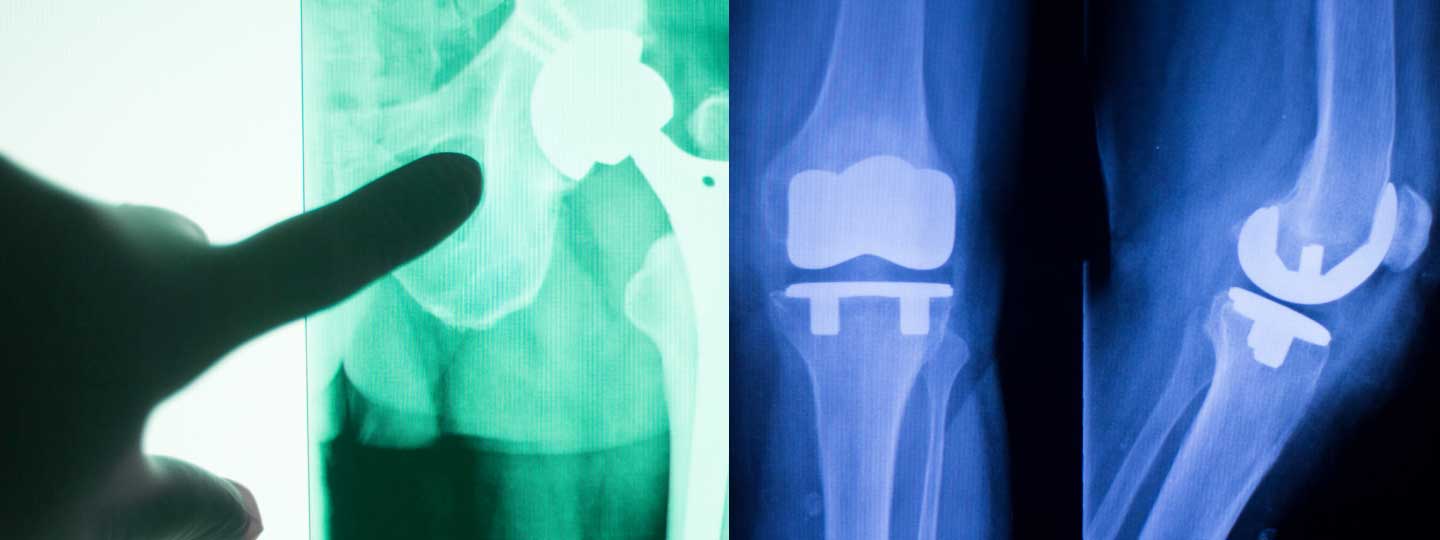

Looking at an x-ray of a hip and knee replacement.